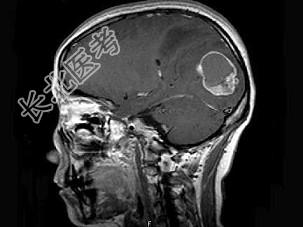

- 单项选择题女,46岁, 头痛、头昏半月入院,根据所提供图像, 最可能的诊断是 ( )

A、转移性乳头状腺癌

B、胶质瘤

C、脑脓肿

D、胶质母细胞瘤

E、毛细胞型星形细胞瘤